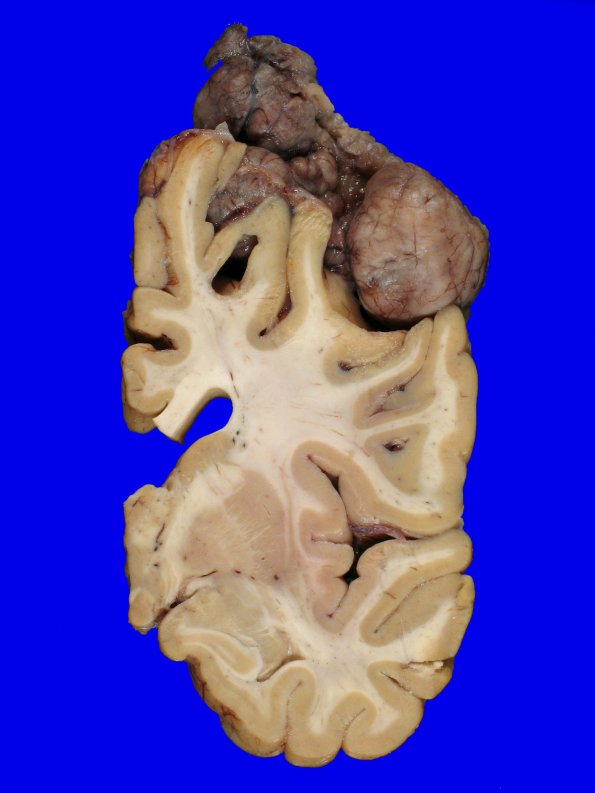

Washington University Experience | NEOPLASMS (MENINGIOMA) | Gross Pathology | 72D8 NCL (Case 72) Gross_18

Additional images of the tumor relationship with the brain.